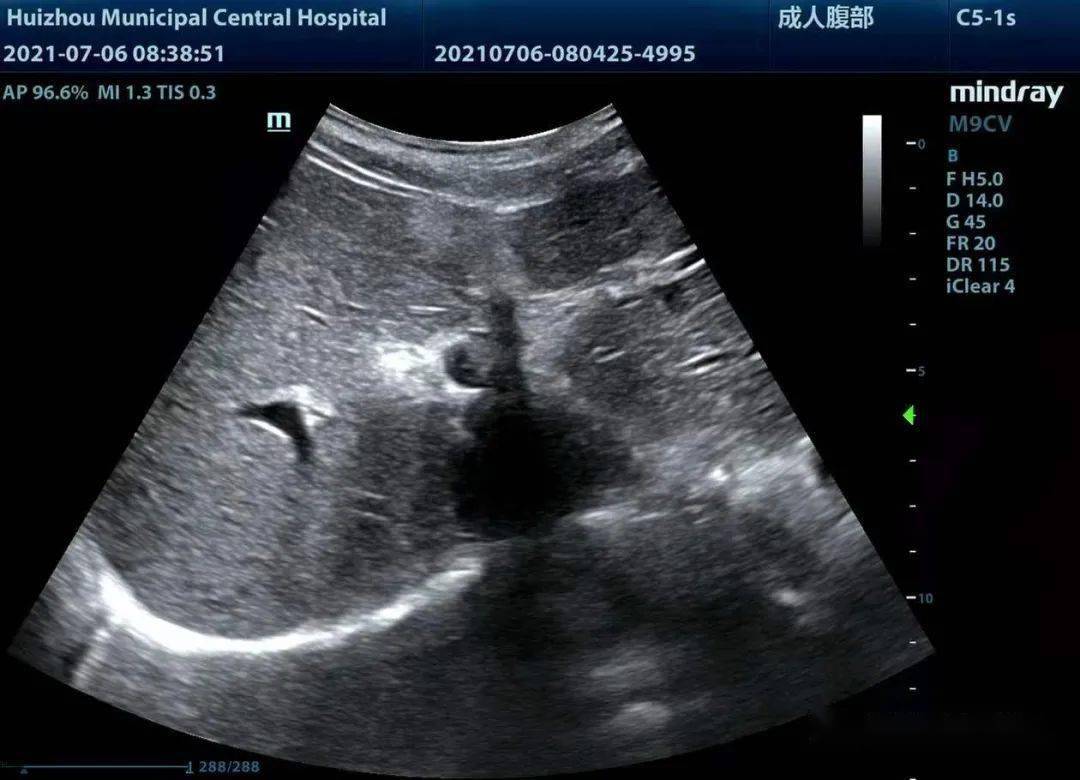

在超声上,肝圆韧带的肝内段我们借助肝脏背景可以很容易观察到,而离开